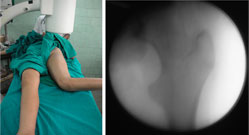

| These pictures were taken in the operating room for better understanding of the rotational deformity. The picture on the left was taken with the foot forward. The picture on the right shows the c-arm picture of the hip joint in the same position. The hip was in extreme internal rotation (normally this would have been in the mid-position, with both the lesser and greater trochanters visible). |

|

This picture on left shows that the knee has been bent to 90º and the hip has been externally rotated to the maximum extent possible.

The c-arm picture on the right was taken with the limb in the position as described above. The appearance of the hip joint is as would be in the frontal (antero-posterior) projection. The lesser trochanter is visible maximally and the greater trochanter is also seen without any overlap. |